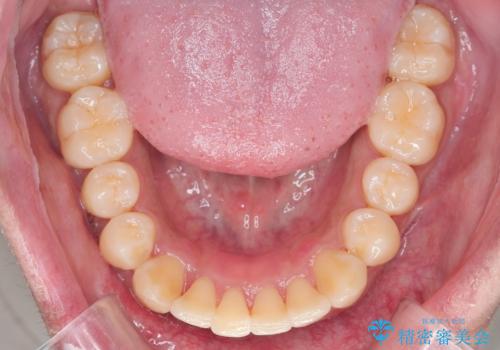

がたつきが気になる。インビザラインでスッキリ。

- インビザラインモデレート

- 奥歯の噛み合わせは特に問題ないため臼歯を特に大きく動かす事はなく。

歯と歯の間を削る(ディスキング)、拡大を行いマウスピースで矯正を行いました。

がたつきもなくなりスッキリした歯並びになりました。

がたつきが無くなると歯ブラシがしやすくなり汚れが溜まりにくい口腔環境ができます。